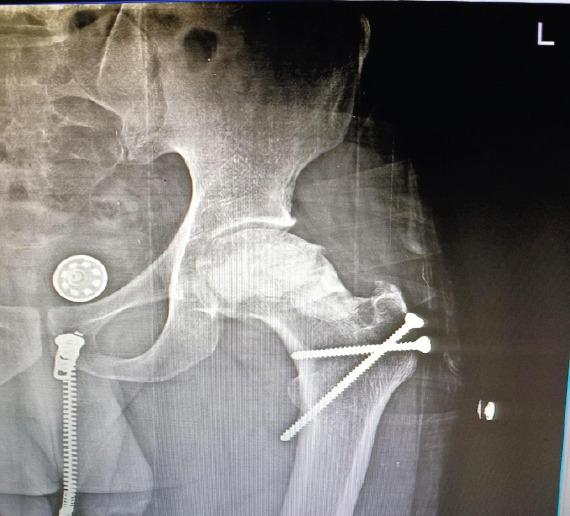

An 18-year-old male patient presented with the left groin pain and terminal restriction of hip movement for 1 year duration. The patient underwent open biopsy and histopathological examination of tissue specimen revealed hydatid cyst. The patient was started on albendazole and after 3 months, surgical curettage and removal of cysts were performed with application of bone cement. At 8 years follow-up, the patient is asymptomatic and doing well.

一名18岁男性患者,左侧腹股沟疼痛并伴有髋关节活动终末受限1年。患者接受了开放活检,组织标本的组织病理学检查显示为包虫囊肿。患者开始服用阿苯达唑,3个月后进行了手术刮除并应用骨水泥去除囊肿。随访8年,患者无症状,恢复良好。